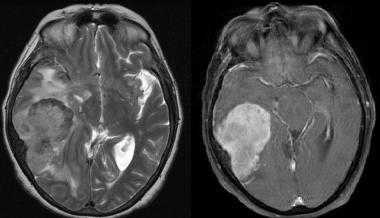

Глиобластома: симптомы, выявляемые с помощью МРТ. Аксиальный срез в режиме Т1 после контрастирования препаратом гадолиния демонстрирует распространенную опухоль правой лобной доли. Изображение предоставлено доктором George Jallo.

МРТ того же пациента. Т2-взвешенное изображение демонстрирует то же поражение, что и на предыдущем рисунке с заметным отеком и смещением срединных структур. Эти находки соответствуют высокой степени злокачественности опухоли.